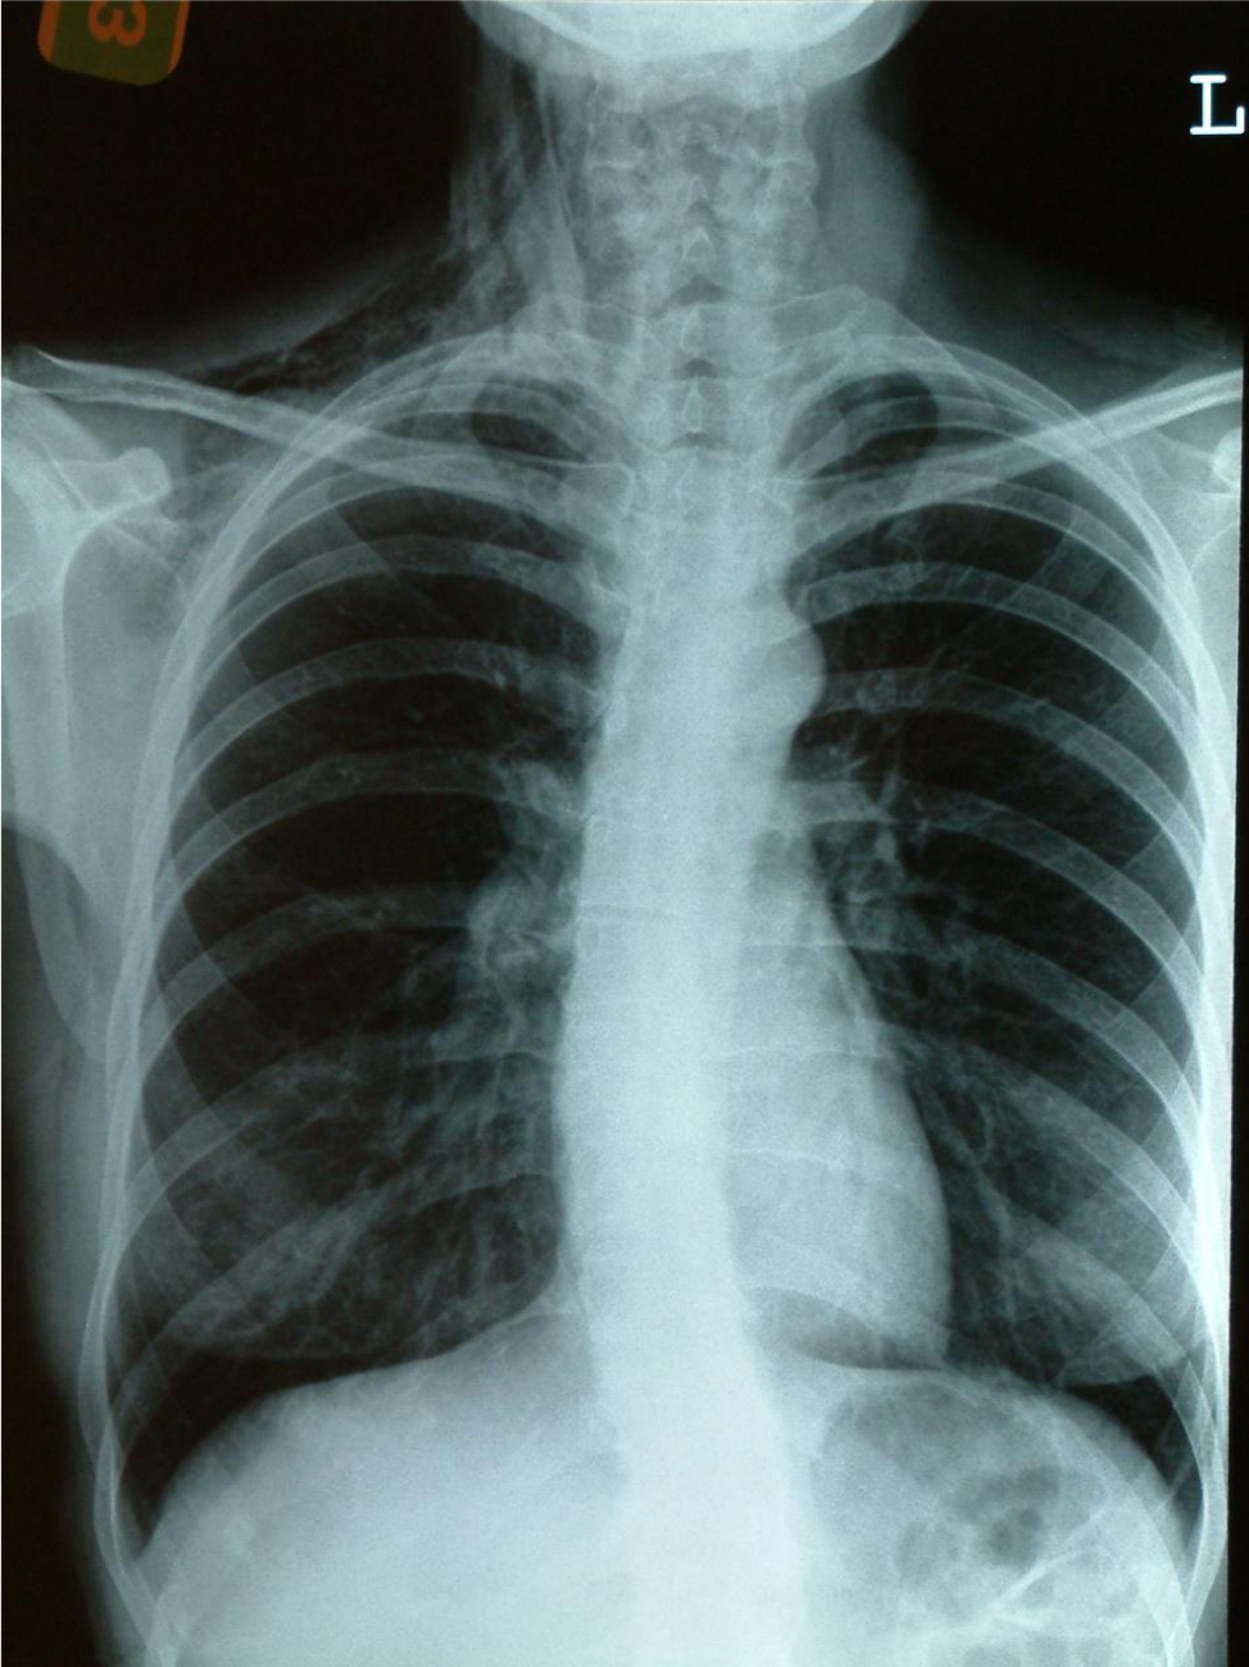

Viêm phổi là hiện tượng viêm nhiễm của nhu mô phổi bao gồm viêm phế nang, túi phế nang, ống phế nang, tổ chức liên kết khe [...]